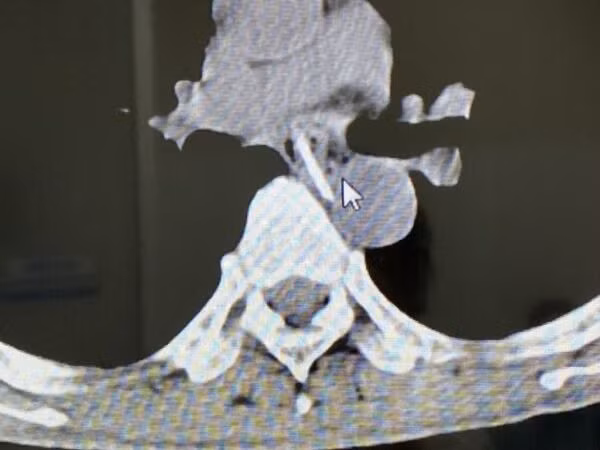

Tại đây, người bệnh được chụp cắt lớp vi tính và nội soi thực quản dạ dày. Các bác sĩ phát hiện, trong đoạn thực quản ngực của bệnh nhân có dị vật là xương gà lẫn thịt có kích thước khoảng 3cm. Xương có đầu sắc nhọn đâm vào thành thực quản.

Trường hợp người bệnh lần này bị hóc xương gà, đầu xương đâm vào thực quản, vị trí xương mắc ở đoạn thực quản ngực ngay sát quai động mạch chủ. Theo TS Đạt, may mắn là người bệnh được đưa đến bệnh viện sớm và đầu xương chưa làm thủng thực quản.